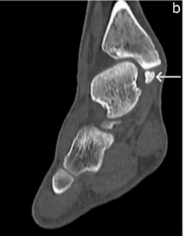

Symptomatic Accessory Ossicle Near the Medial Malleolus Simulating Fracture Non-union: A Case Report and Literature Review

Rajesh K Rajnish , Akshant Chandel , Sandeep Kumar Yadav , Abhay Elhence , Prabodh Kantiwal , Kartikey Dubey

………………………………p.252-257